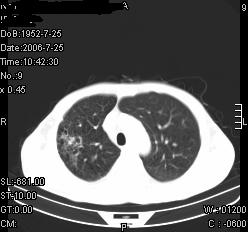

患者,男,54岁,咳嗦,咳痰20天。抗炎治疗2周。现esr76mm/h,目前患者症状明显好转,但发现两次ct片未见明显变化。两次分别做与7.25、7.31。第一次诊断右肺上叶炎症累计胸膜。大家看,从影像上内排除结核吗?

结核的可能性非常大,右上肺病变应该考虑干酪性肺炎。理由:

1.纵隔内多发淋巴结肿大。

2.esr76mm/h。

3.虽经抗炎治疗肺窗病灶有所吸收、减小,但纵隔窗病灶形态、密度、范围无明显变化。如果是单纯的大叶性肺炎,“抗炎治疗2周,目前患者症状明显好转”病灶应该基本消散了,至少也处于吸收消散期,密度变淡、范围变小。同时本病例所示其内的密度不均匀,见多发大小不一空洞样影也不符合大叶性肺炎吸收消散期表现。

病灶特点:片状 索条 结节混杂影,部分融合,密度不均,广泛累及相应胸膜.

临床治疗;二周未吸收.但症状好转.

多考虑:肺结核.